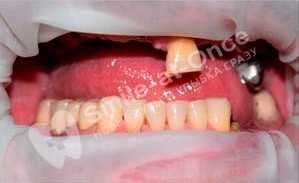

Чорный Станислав Владимирович: портфолио (25)

Имплантация

Для восстановления жевательных зубов потребовалось проведение имплантация полной челюсти по причине плохого состояния зубов на всей челюсти.